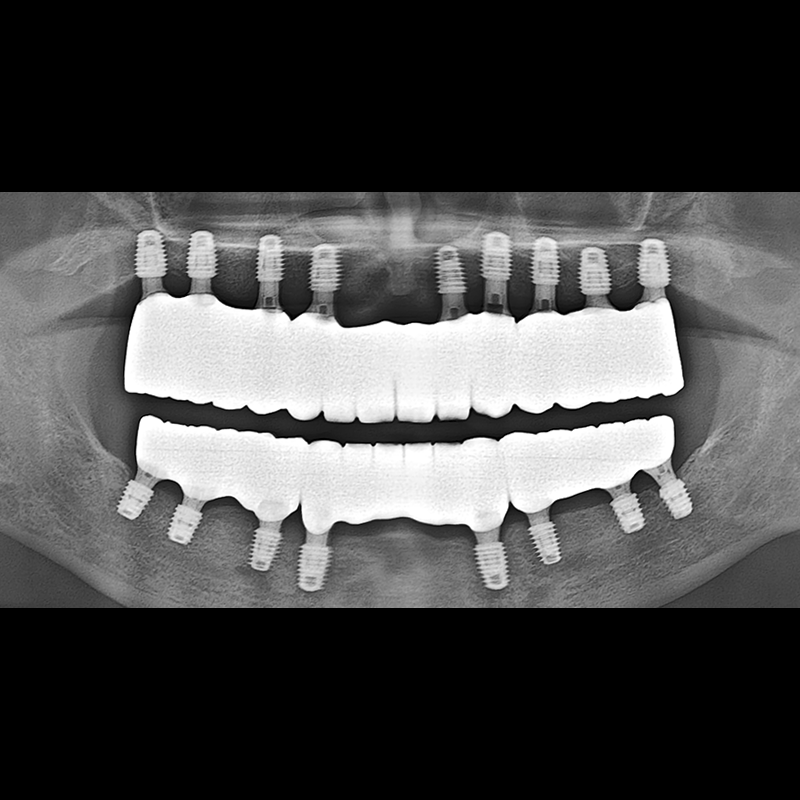

BEFORE AFTER

Implant before and after 2025.05.30

Implants were placed in the missing tooth and in the tooth position where it was difficult to save.